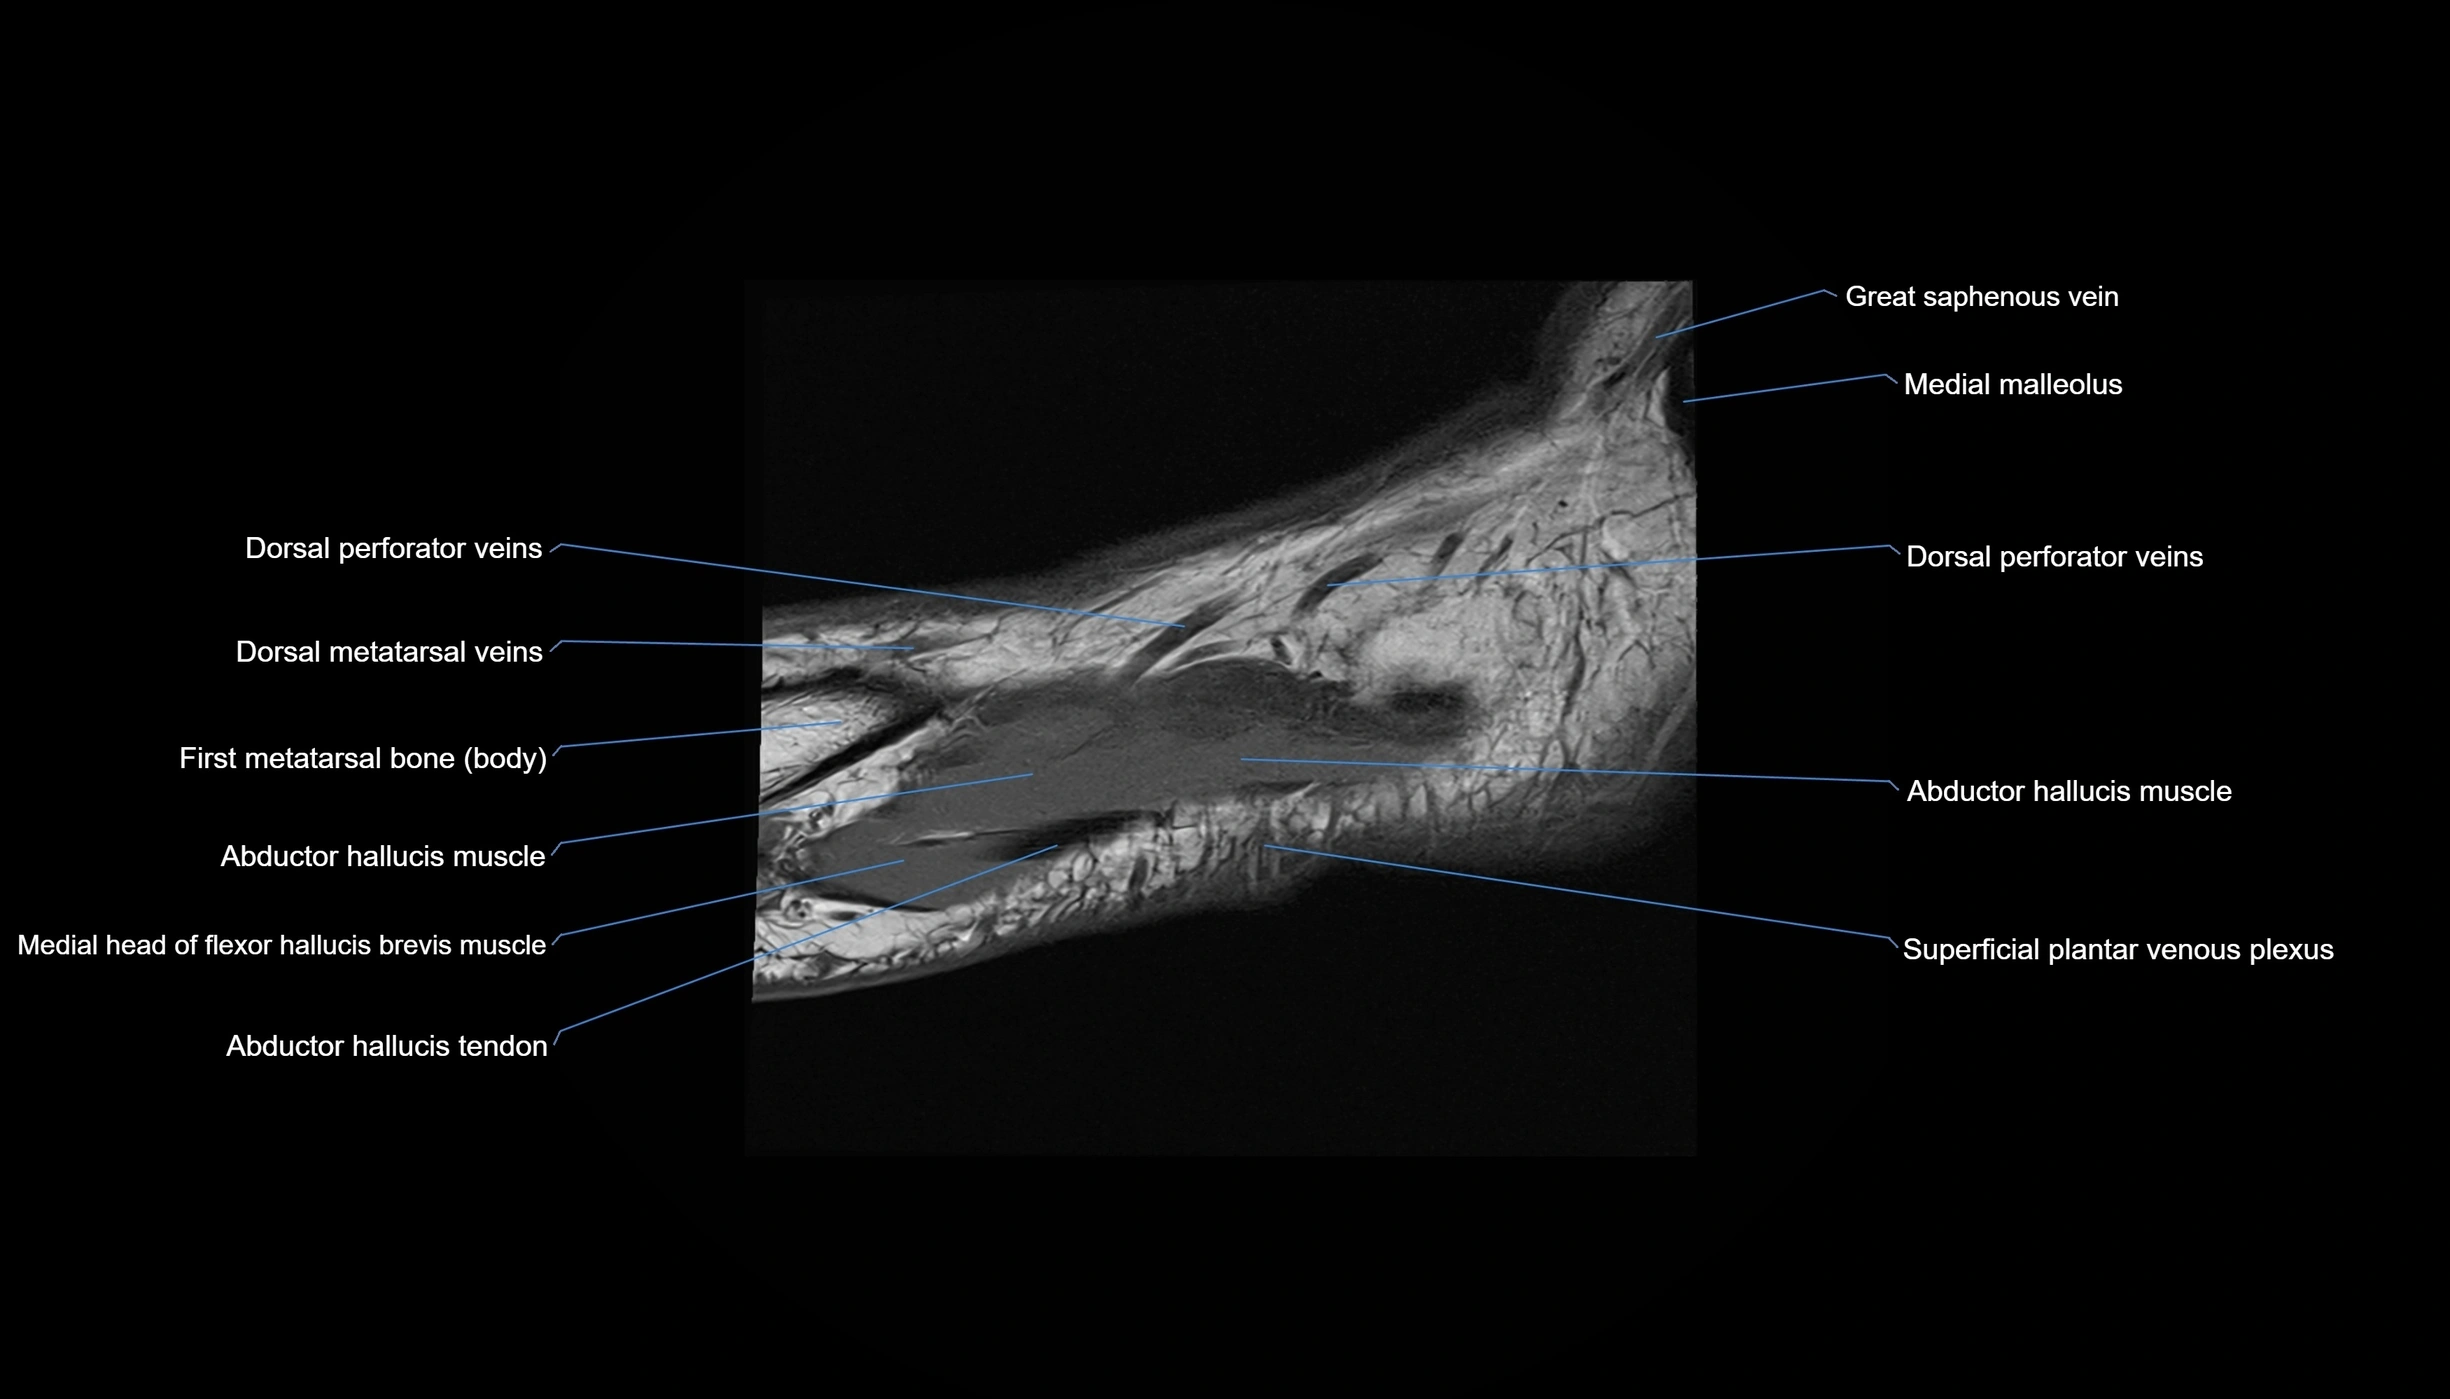

MRI image